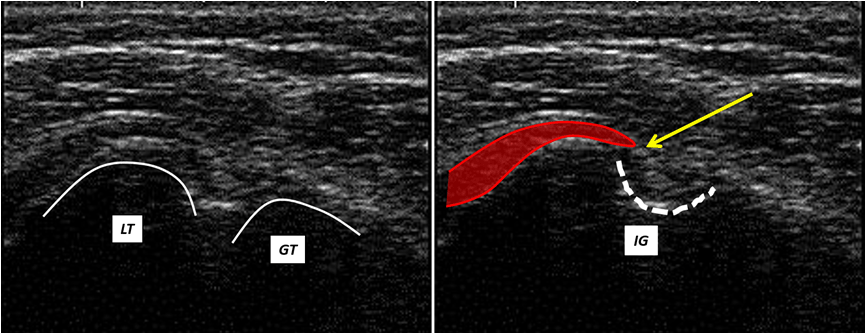

The ultrasound transversal view can be classified into four types (Figures 1,2,3,4).

Figure 2: Ultrasound transversal view Type II: The fibers (yellow arrow) of the SCM tendon insert into the IG of the humerus (close to the LHBM tendon); LT = lesser tubercle; GT = greater tubercle; IG = intertubercular groove.